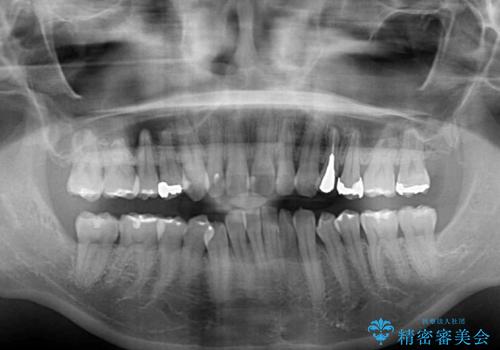

- 学生の頃に矯正治療を行ったものの、保定を怠けてしまったことによる後戻りを気にして来院された患者様です。

根管治療が必要な歯があったため、矯正治療前に根管治療を行い、その後はインビザラインにより矯正治療を行うこととしました。

矯正治療後には根管治療を行った歯の補綴治療を行うこととしました。